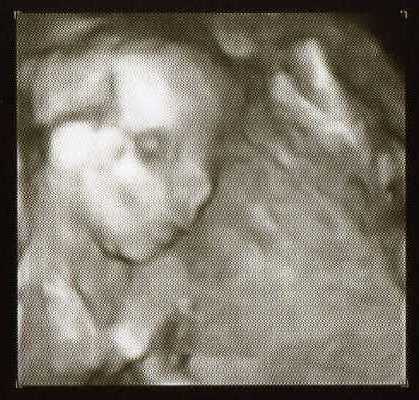

Oto portrety naszego Kubusia z 20 tygodnia:-)

Waży 340g

• 4d.jpg

4d.jpg